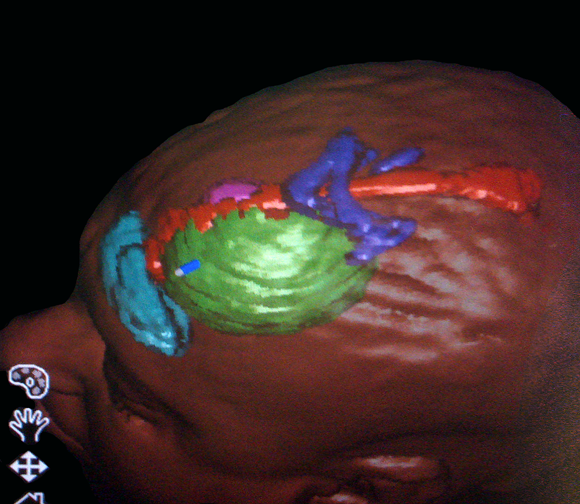

Στο μοντέλο αυτό μπορούν να συνεισαχθούν και πληροφορίες από άλλες ακολουθίες της μαγνητικής τομογραφίας, π.χ. λειτουργικές ακολουθίες όπου απεικονίζονται θέσεις κέντρων του λόγου ή της κίνησης ή ακολουθίες δεσμιδογραφίας όπου απεικονίζονται νευρικές οδοί στο βάθος του εγκεφάλου. Ο χειρουργός έχει έτσι την δυνατότητα να σχεδιάσει προεγχειρητικά την επέμβαση, αποφεύγοντας για παράδειγμα προσπελάσεις που αυξάνουν τον κίνδυνο τραυματισμού ευγενών περιοχών του εγκεφάλου ή μεγάλων αγγείων. Η ταύτιση του ψηφιακού μοντέλου με τον προεγχειρητικό σχεδιασμό και της πραγματικής ανατομίας γίνεται στο χειρουργείο με την

Δεσμιδογραφία (DT MRI) εγκεφάλου

Navi6

βοήθεια ειδικού εξοπλισμού και το τελικό αποτέλεσμα προβάλλεται στην οθόνη του νευροπλοηγού και στο χειρουργικό μικροσκόπιο καθ' όλη τη διάρκεια της χειρουργικής παρέμβασης.